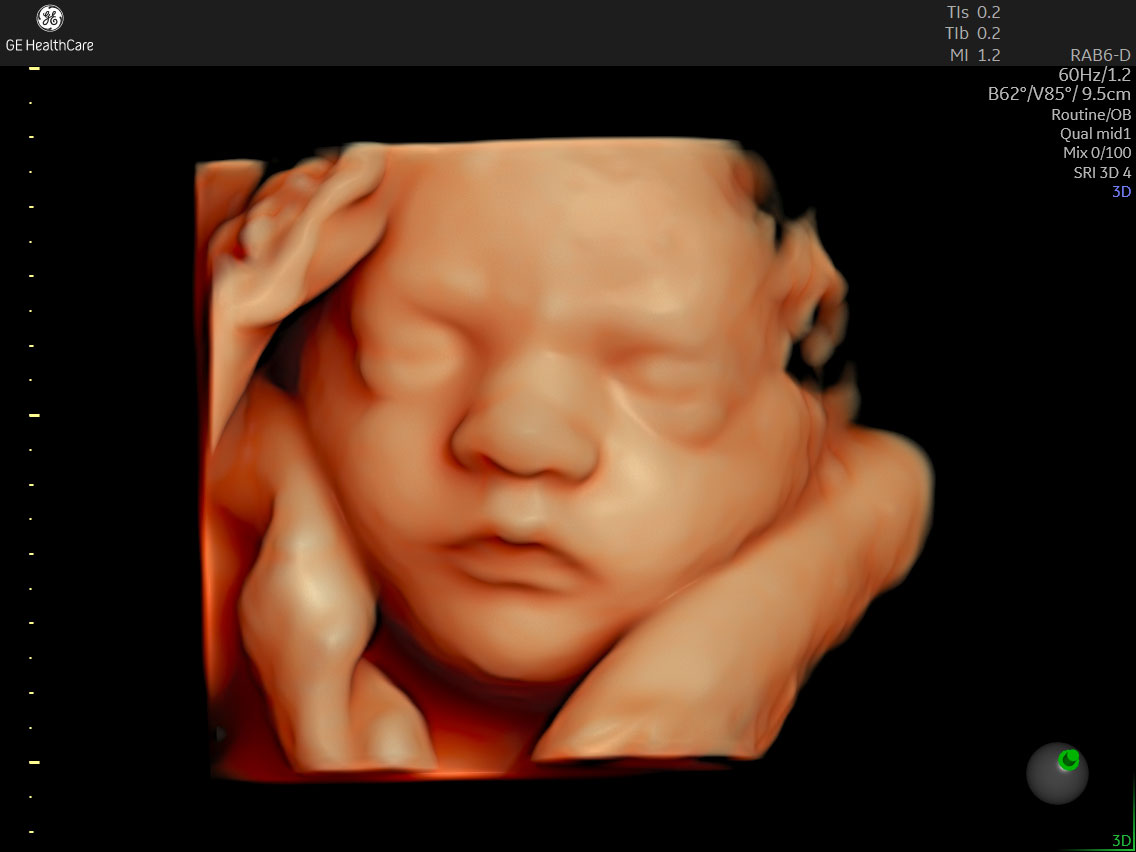

超音波検査装置

GE volson Signature 18

鮮明な4Dエコー画像をご覧いただける超音波検査装置です。

撮影した画像はQRコードで保存ができますので、おなかにいる赤ちゃんの画像をお持ち帰りいただけます。